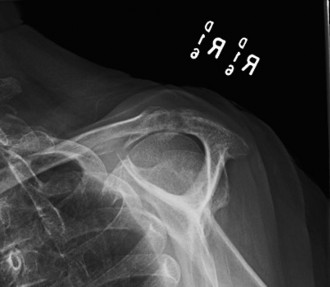

--- _Figure 2–30_A: Axillary view. B: Axillary view with annotations. Traumatic anterior instability is a common shoulder problem with an estimated incidence of 1.7%. This term encompasses both frank dislocations that require a manual reduction as well as incomplete subluxations that spontaneously reduce. It is particularly common in the young and athletic population, and it is significantly more common than other forms of instability including posterior or multidirectional instability. Understanding the natural history of anterior instability is important, as it serves as a guide to treatment. Young patients have a very high risk of recurrence; patients <20 years old have a 90% recurrence risk, between 20 and 40 years old have a 60% recurrence risk, and >40 years old have a 10% risk. Recurrent events are a predictor for arthritis and necessitate aggressive treatment, particularly in the young patient.